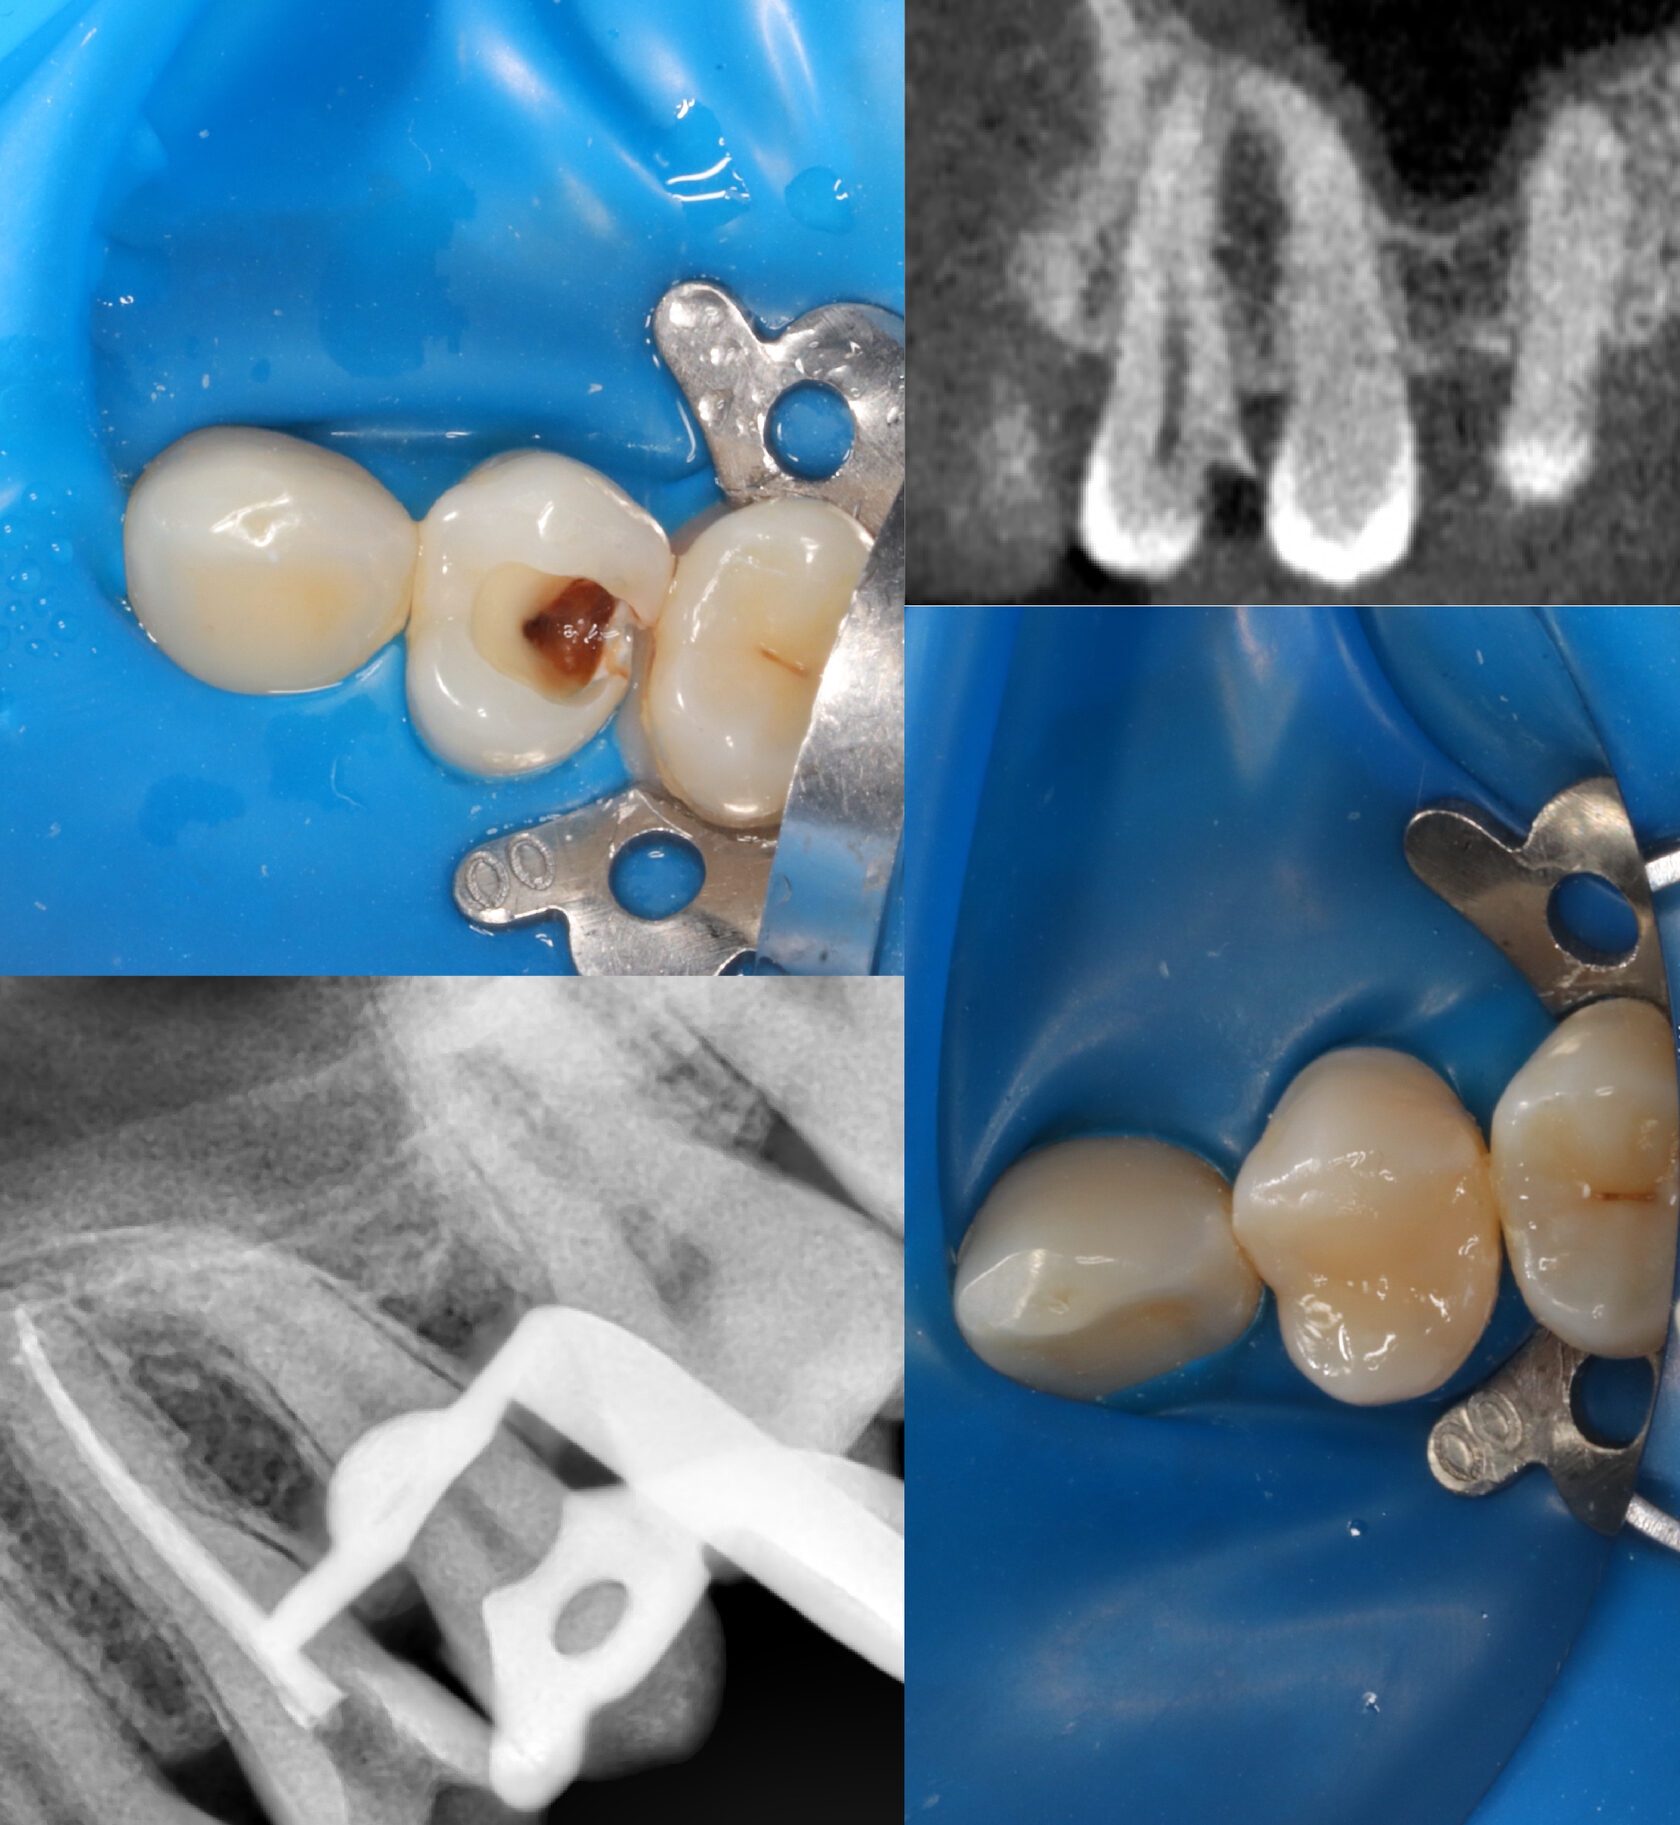

Пациент обратился к нам с профилактическим осмотром, на котором на зубе обнаружена небольшая кариозная полость, что также подтверждается снимком. Полость действительно небольшая, это означает, что кариес не добрался до нерва и требуется лишь постановка пломбы.

Но пациент на данном этапе не начал лечение, в связи с тем, что зуб не беспокоил. Спустя 1,5 года пациент обратился уже с жалобой на постоянную ноющую боль в этом же зуба, которая мучала его все новогодние праздники! Не самое приятное ощущение, правда?

При осмотре и на снимке мы видим уже совсем другую картину. кариозная полость сильно углубилась и достигла нерва, поэтому зуб давал такую сильную боль.

На данном этапе, имея сильную боль и неприятную реакцию на холодную воду, пациент согласился лечить зуб, потому что если подождать еще 1,5 года, то можно его потерять.

Нами было проведено эндодонтическое лечение внутренностей зуба, предварительно восстановив сломанную стенку и изолировав зуб от слюны.

Эндодонтическое лечение проводилось согласно клинических рекомендаций ВОЗ и протоколов нашего центра. Корневые каналы промыты, избавлены от очага инфекции и плотно запломбированы, что подтверждается на контрольном снимке.